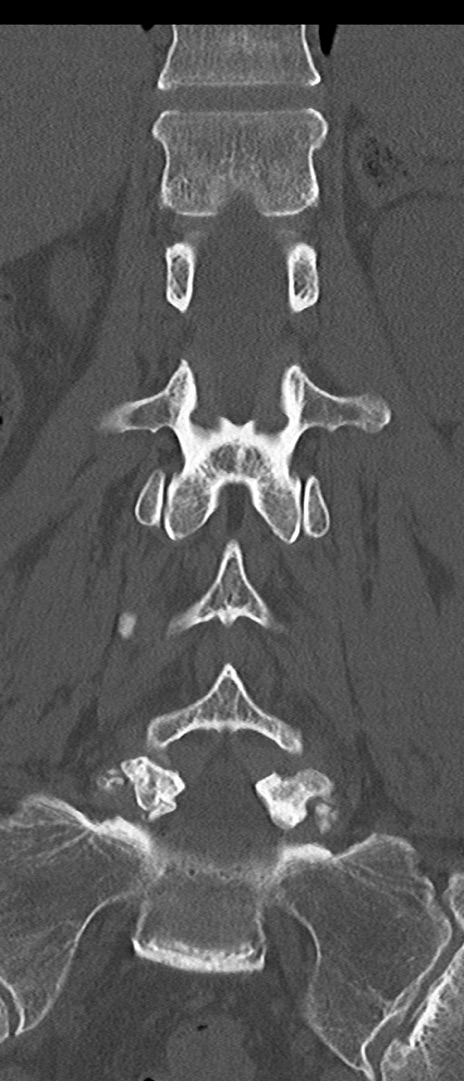

【整形】TIPS症例4 腰椎CT(冠状断像)

腰椎CT

矢状断像